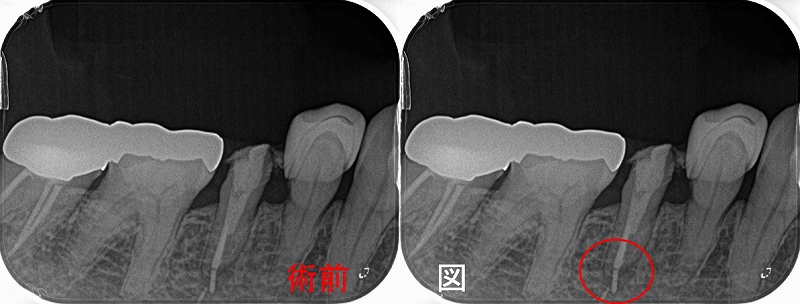

術式の差による骨の治り

たまにある側切歯の大きな病変(レントゲンのこの黒い部分は細菌由来の炎症で骨がありません)

2026 EEdental INA (1).jpg

意外と側切歯の根尖病変は大きくなりやすいのと、前歯の中で予後が最も悪い歯なので

前歯を残したい方は神経の治療は歯内療法専門医に任せた方がいいと思います。

以前の治療で根管内を太く削ってあったので外科的歯内療法を選択しました。

2026 EEdental INA (2).jpg

だいぶ大きく骨が無くなっておりスルー&スルー(唇側から裏側までトンネル状に骨がない)の状態でした。

こうなると骨が治る足場が無く骨の治りは遅くなります。

2年予後

2026 EEdental INA (3).jpg

スルー&スルーで貫通した部分にはまだ透過像があります。。。

ただ、膿や腫れはなく経過は良好です。